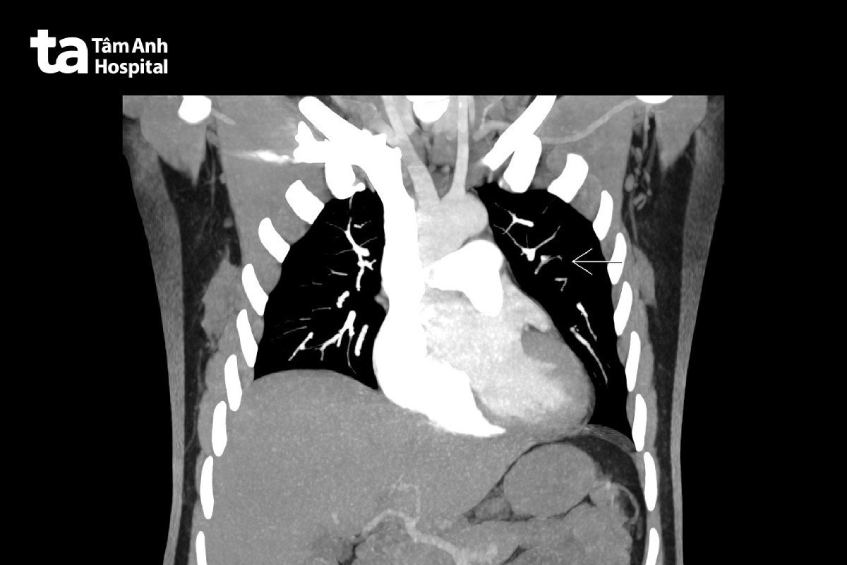

Tại đây, kết quả siêu âm cho thấy huyết khối kèm u xơ tử cung rất lớn, to bằng thai 30 tuần, thiếu máu nặng. Xét nghiệm máu, chỉ số hemoglobin còn 7g/dl (nữ bình thường là 12.5 – 14.2g/dl), phải truyền máu khẩn cấp. Người bệnh được chỉ định CT tiêm thuốc cản quang phát hiện, u xơ tử cung chèn ép dãn niệu quản và ứ nước thận phải, có huyết khối ở tĩnh mạch 2 chân, có huyết khối trong động mạch phổi.

Xác định đây là trường hợp khó, hiếm gặp, bệnh viện tiến hành hội chẩn nhiều chuyên khoa, lên phương án điều trị cho người bệnh. Trước phẫu thuật, bệnh nhân được truyền máu bổ sung, sử dụng thuốc kháng đông ngăn ngừa sự hình thành huyết khối. Bác sĩ Trung tâm Tim mạch tiến hành can thiệp đặt lưới lọc vào tĩnh mạch chủ (IVCF) ngăn chặn tình trạng di chuyển huyết khối từ 2 chân và tĩnh mạch chậu về buồng tim và tuần hoàn phổi.